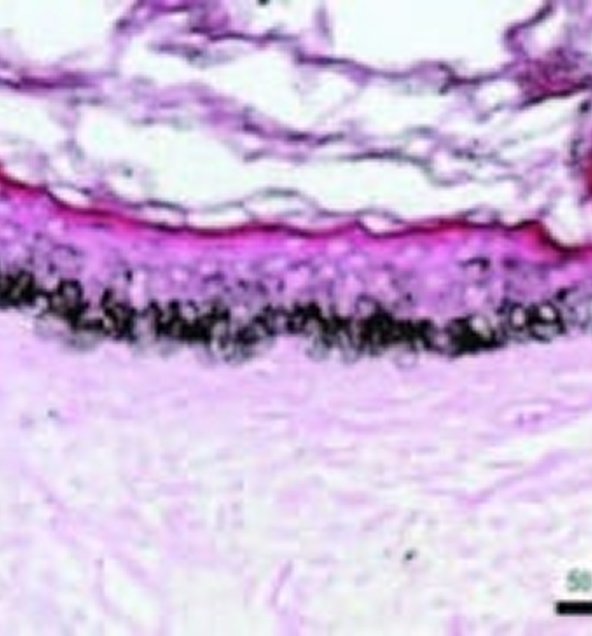

- This DEJ-shallow dermis area is the target depth to microneedle. See arrows where microchannels are formed

Epidermal melanin density in melasma before procedure

Reduction in epidermal melanin density 1 week after microneedling procedure